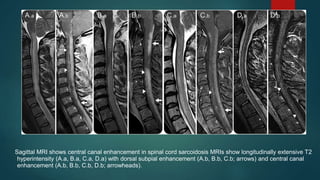

Sagittal MRI shows central canal enhancement in spinal cord sarcoidosis MRIs show longitudinally extensive T2

hyperintensity (A.a, B.a, C.a, D.a) with dorsal subpial enhancement (A.b, B.b, C.b; arrows) and central canal

enhancement (A.b, B.b, C.b, D.b; arrowheads).

Axial postgadolinium images

highlight the trident sign

Crescent-shaped layering of

posterior subpial enhancement

accompanied by central canal

enhancement led to a 3-pronged

appearance (A.a, B.a, C.a)

resembling a trident head (A.b,

B.b, C.b).